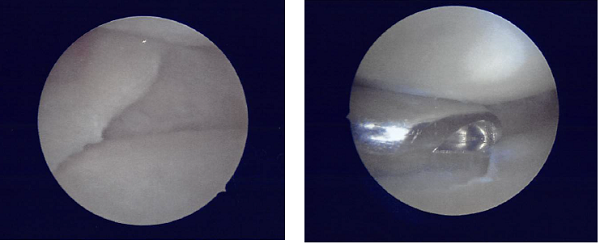

A lateral entry portal was made and an arthroscope was inserted. Examination of the knee showed a tear of the medial meniscus posterior horn.

A medial working portal was made using a spinal needle followed by an incision. Further examination of the knee showed a cyclops lesion of the ACL as well as medial frayed margins of the lateral meniscus.

There was grade 1 to· grade 2 osteoarthritic changes in the medial femoral condyle as well as grade 3 to grade 4 osteoarthritic changes in the trochlea. The tear of the medial meniscus was compact and was not repairable.